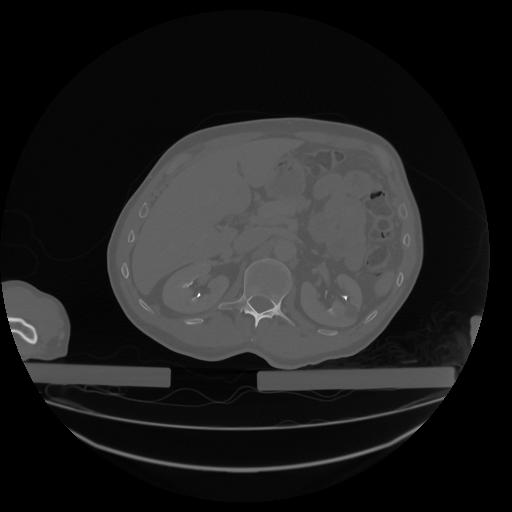

34 CUERPO,CE,Vol,1.0,CUERPO,,